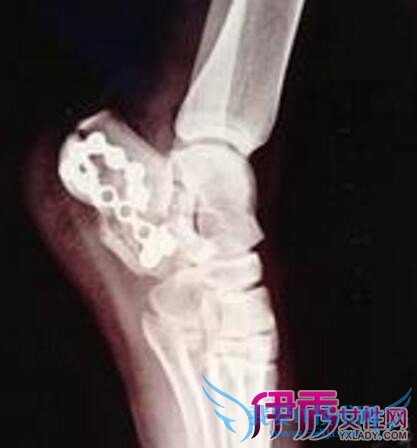

脚后跟粉碎性骨折属于完全性骨折,指骨质碎裂成三块以上,又称为t或y型骨折开放性骨折是指骨折处皮肤或粘膜破裂,骨折端与外界相通。股骨部位粉碎性骨折会使人变成瘸子。

粉碎性骨折就是断骨处断裂成几块,如果选用石膏固定,骨头接上,稍有错位,就会留下后遗症,再说石膏并不能固定正骨,因为石膏是软体的,只是在原有的基础上固定而已,石膏上久了,会使关节僵硬,无法弯曲,对以后的生活带来诸多不便。

建议用夹板体外固定复位,然后选用野生草药外敷快速接骨,一般3天就可接上,骨头接上时疼痛明显减轻80%左右,再用药保养15到20天就可痊愈。不会留下后遗症。在治疗期间,不要过多活动患肢,以免影响骨头的愈合,忌吃含激素的药物。